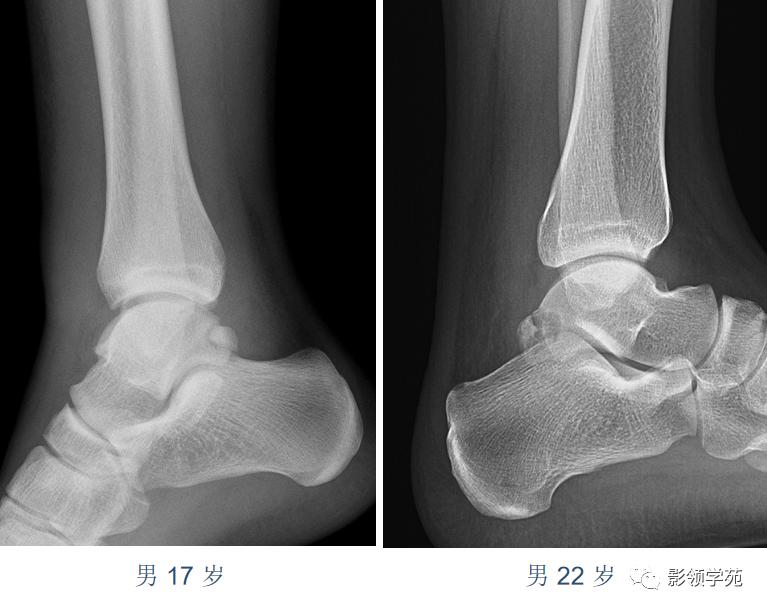

籽骨、副骨、永存性骨骺可发生于人体全身骨关节,而四肢关节最多见且最复杂, 加之对其分布认识的不足和临床经验的欠缺,平时工作中易误诊为撕脱骨折。有鉴于此,今天通过对一些案例的分析,初步归纳他们相互鉴别的要点。

虽然撕脱性骨折与永存骨骺、籽骨和副骨在影像学上均有游离的小骨块影的表现,但前者具有骨折的影像学一般特征,而后三者不具有。

永存骨骺、籽骨和副骨的发生与其特有部位及典型特征紧密联系。

常见案例均具有骨块边缘钝圆、骨皮质连续、局部软组织无明显肿胀以及伤后该骨的连续摄片无明显变化等非撕脱性骨折的共同特点。

鉴别重点:独立的骨结构(游离骨)若与相对骨的缺损缘相吻合,是撕脱,如有外伤,更支持。